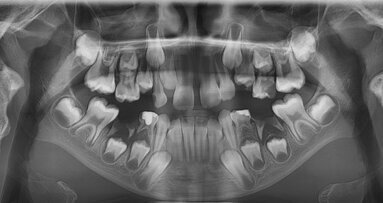

Ankieta udostępniona na początku Narodowego Miesiąca Uśmiechu, zlecona przez Oral Health America ujawniła, że 4 na 5 dorosłych zgadza się, że świadczenia stomatologiczne są tak samo istotne jak świadczenia ogólnomedyczne w pakiecie świadczeń całościowej opieki zdrowotnej. Wielu ubogim rodzinom w USA, a także pochodzącym z niższej klasy średniej, obecnie nie udziela się potrzebnych świadczeń stomatologicznych, m.in. dlatego, że dentyści preferują pacjentów z prywatnymi ubezpieczeniami lub płacących gotówką. Najnowsze dane pokazują także, że niedostatek opieki stomatologicznej nie jest ograniczony tylko do ludzi ubogich. Eksperci z zakresu zdrowia jamy ustnej twierdzą, że ok. 100 mln Amerykanów nie ma dostępu do odpowiedniej opieki.

American Dental Association (ADA), reprezentująca ponad 157.000 dentystów w USA, w ostatnim liście do prezydenta USA, wzywa rząd do poświęcenia większej uwagi opiece stomatologicznej w trwającej debacie nad polityką zdrowotną. W liście ADA stwierdza: „Przyznając, że większość Amerykanów ma dostęp do doskonałej i względnie niedrogiej opieki stomatologicznej, musimy podkreślić, że zbyt wielu Amerykanów o niskich dochodach nadal niepotrzebnie cierpi z powodu chorób zębów. Należy zrobić więcej w celu zapewnienia wszystkim Amerykanom dostępu do wysokiej jakości świadczeń stomatologicznych”.

ADA zaleca zwiększenie funduszy przeznaczonych na ogólnokrajowy program zdrowotny Medicaid, odbudowujący infrastrukturę zdrowia publicznego w zakresie zdrowia jamy ustnej i wspierający oparte o potrzeby społeczne środki zapobiegawcze, tj. fluoryzacja i szkolne programy edukacyjne.